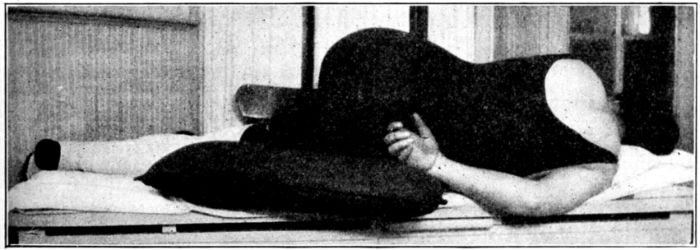

| 42. | Gloves, ready for dry sterilization | 160 |